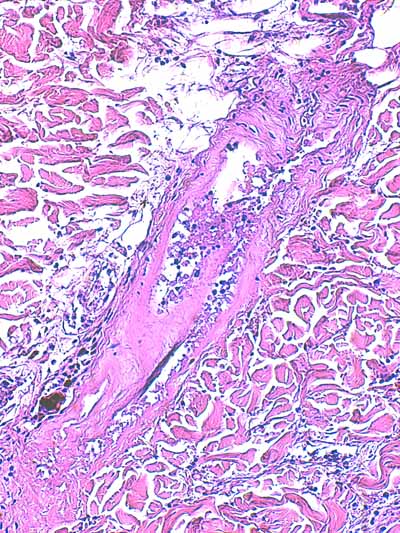

Photo 7 (Hémalun-Eosine X40) : l’hypoderme et le muscle peaucier sont dilacérés

par l’œdème et un infiltrat cellulaire diffus. Un vaisseau sanguin de moyen calibre contient un thrombus fibrineux.

Légendes de la Photo 7 :

- Flèches turquoises : muscle peaucier

- Flèches juanes : œdème et infiltrat neutrophilique dilacérant l’hypoderme et le muscle peaucier

- Ovale turquoise : la lumière d’une veine de moyen calibre est obstruée d’un thrombus fibrineux

- Double flèche verte : épaisseur dermique

- Double flèche bleue : épaisseur hypodermique

- Étoiles bleues : follicules pileux